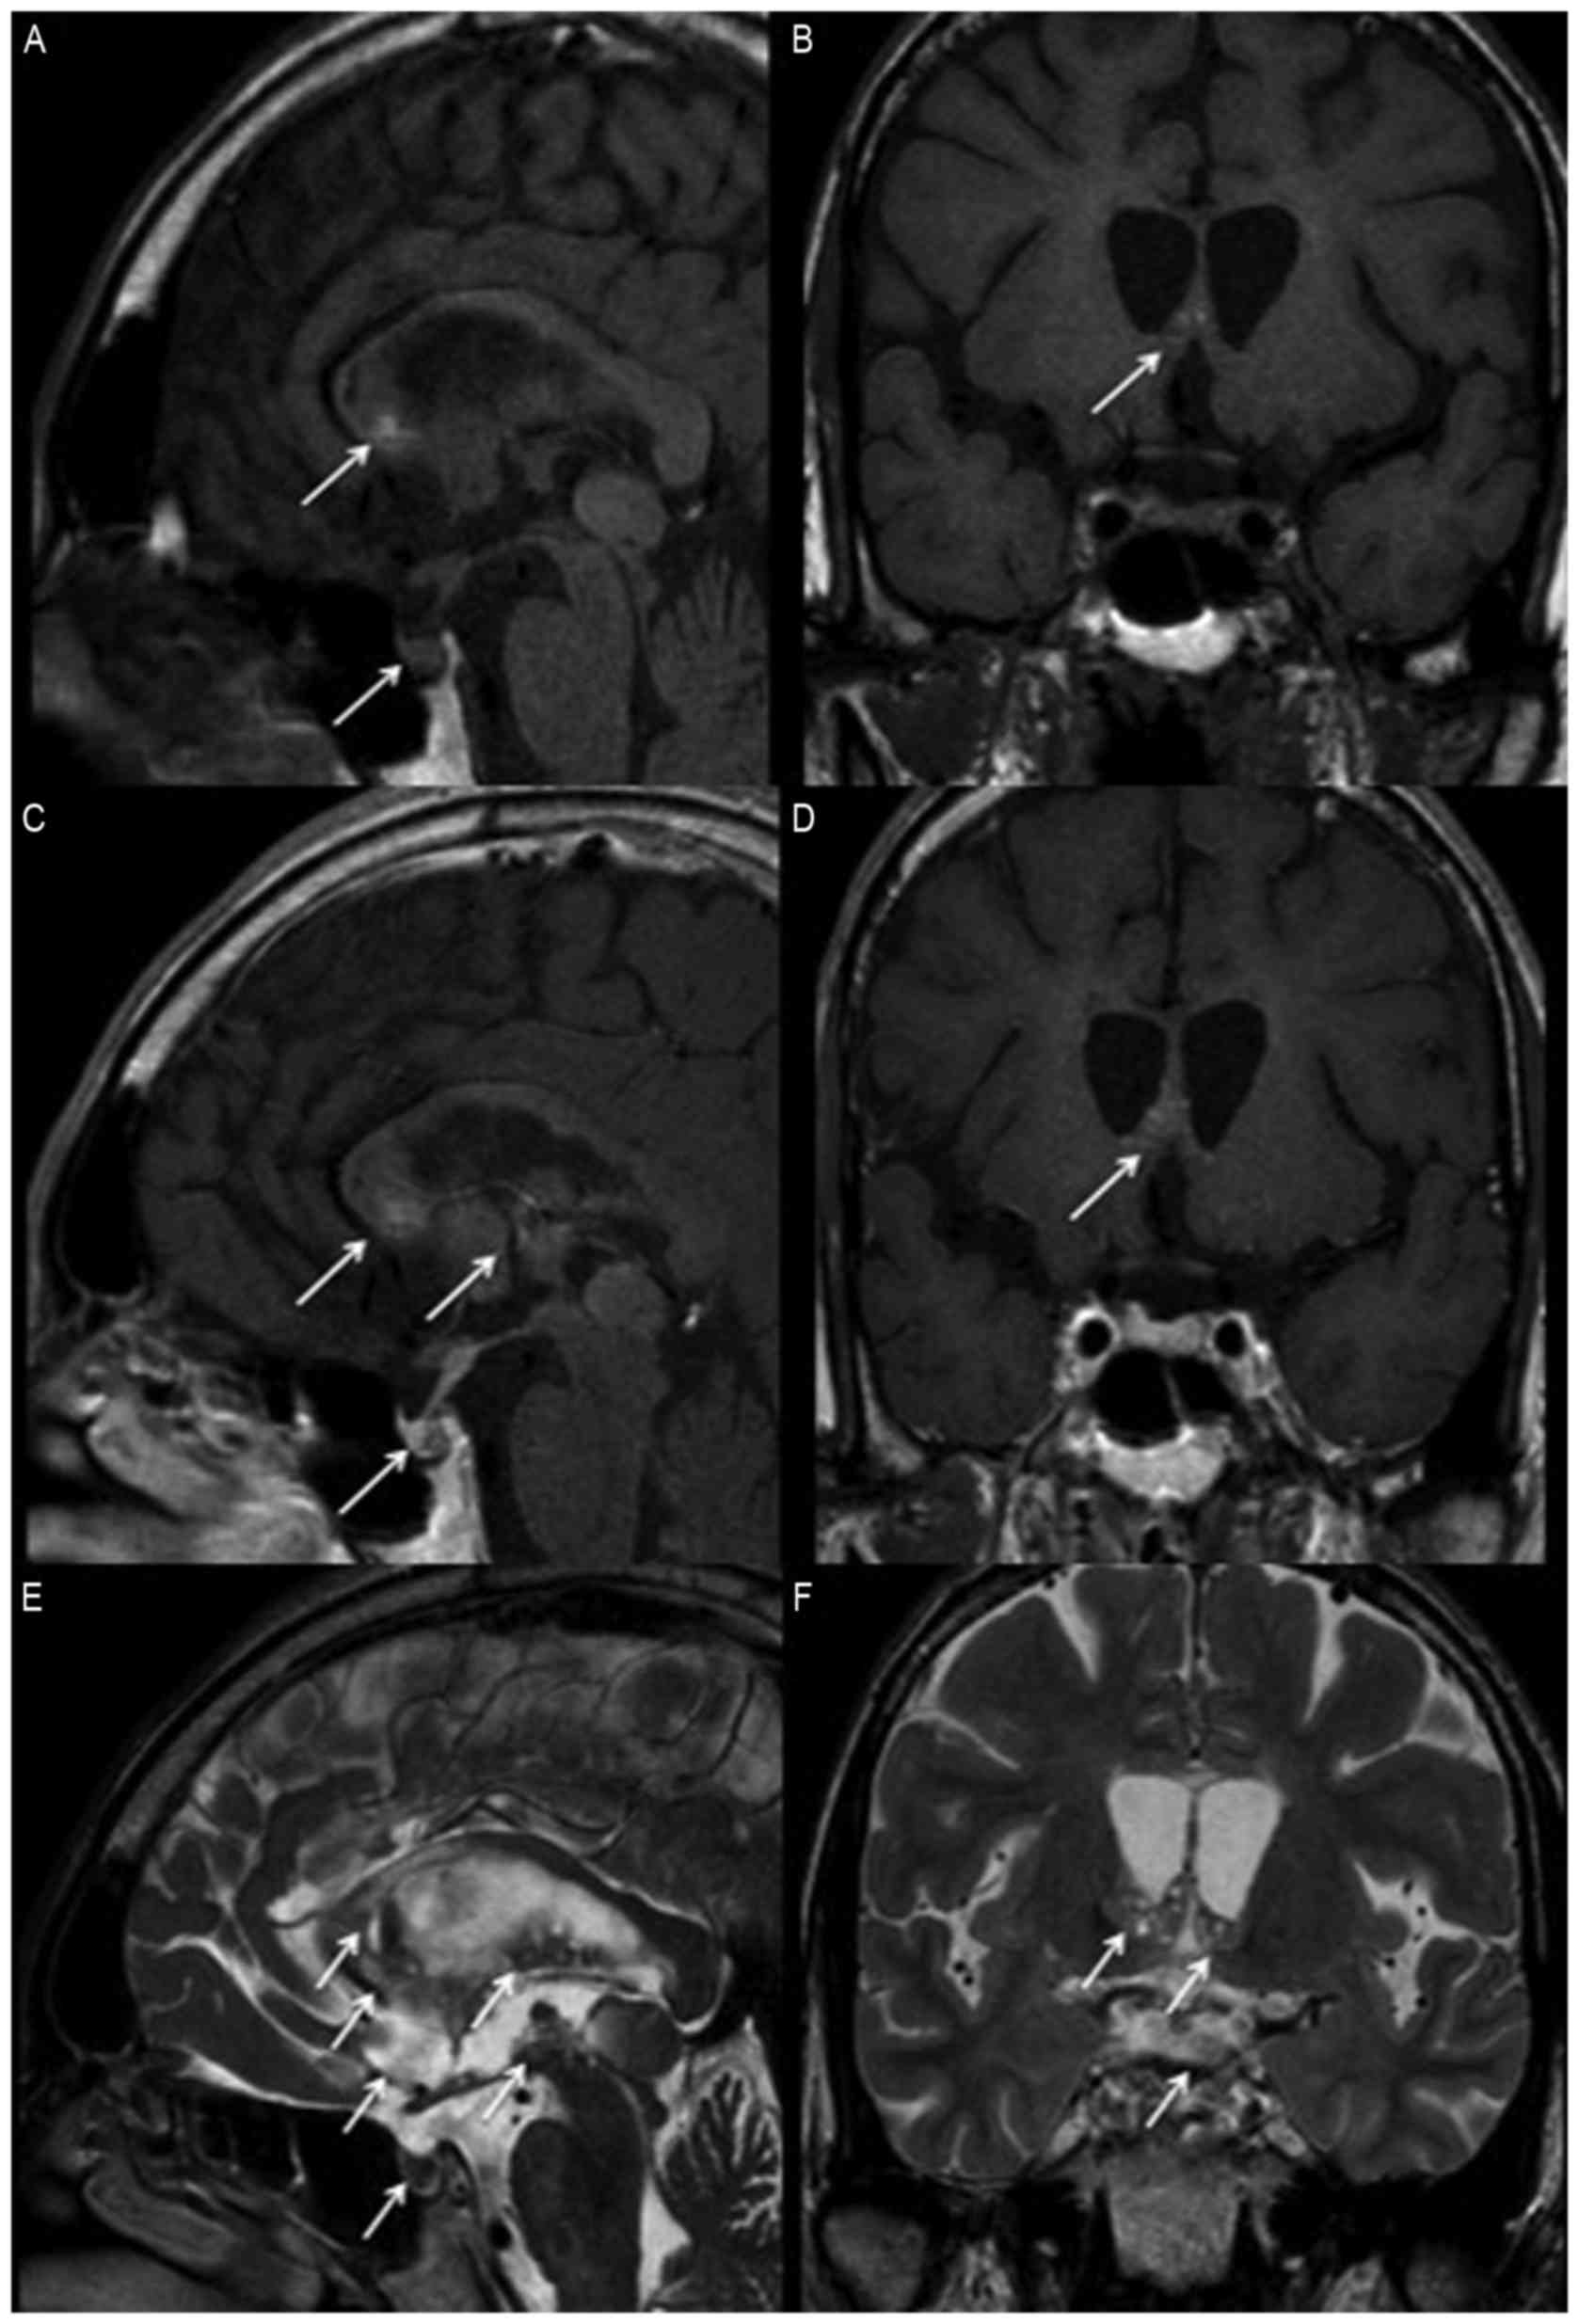

Following 6 cycles of chemotherapy and radiotherapy, a brain MRI scan revealed that the tumors markedly decreased in size (Fig 2). The serum β-hCG levels of the patient fell to 0.3 IU/l and hyperandrogenemia subsided, with testosterone levels recorded as 84 ng/dl. However, the psychological symptoms of the patient, including irritability and emotional instability, only improved a little.

Figure 2.

Magnetic resonance imaging of suprasella two years following treatment. The tumors over the basal ganglion, hypothalamus, corpus callosum, posterior hippocampus, pineal gland, stalk and posterior pituitary gland have disappeared, as indicated by arrows, in (A) non-contrast sagittal, (B) coronal, (C) contrast sagittal and (D) coronal T1 weighted images, as well as (E) T2 weighted sagittal and (F) coronal images.